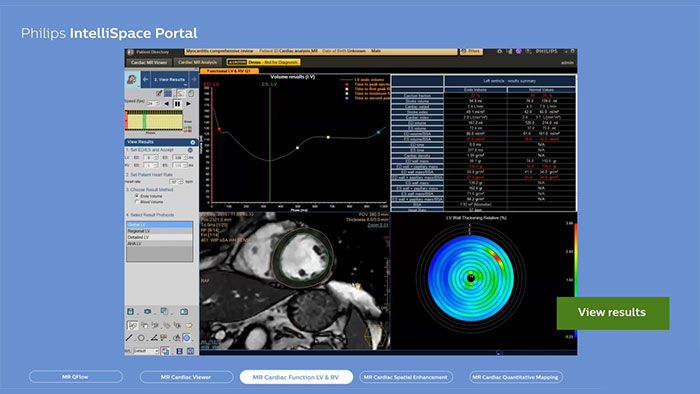

MR Cardiac for detailed quantification of cardiac function

Discover how Advanced Visualization Cardiac clinical portfolio helps you assessing myocardial function, volume, and scaring.

MR Cardiac

Detailed quantification of cardiac function

Includes a viewer and functional analysis. The MR Cardiac Viewer allows side-by-side review of single, multiple or all available cardiac series in a default or in a user-defined viewing protocol. It automatically links multiple series in respect to DICOM geometry, zoom/pan, time and position link for qualitative assessment and analysis in AHA 17 segment templates of the MRC data types. It supports basic measurements and screen captures.

Benefits

- The application provides semi-automatic and manual tools for segmentation.

- Results are calculated based on the Simpson method. The user has an option to apply automatic papillary muscles extraction if desired.

- Results tables can be configured by the user, and values indexed by Body Surface Area (BSA).

- RV segmentation workflow is simplified to be harmonized with LV, and enhance visibility of the phase-prorogation capability.

- Left ventricle volumetric analysis based on single or multi-slice, multi-phase or real-time dynamic 2 Chambers and/or 4 Chambers long axis image acquisitions is also supported based on the Area Length Ejection Fraction (ALEF) single or bi-planar method.

- All results and screen captures can be collected, saved and exported by the user in a Findings Navigator functionality.